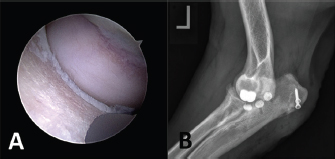

In all five cases with persistent lameness and pain, a second look arthroscopy was carried out. In two cases, an extension of a full-thickness chondral defect caudal to the ulnar implant was apparent and treated by implantation of one (n=1) or two (n=2) additional UImpl just caudal to the initial implant along the ulnar trochlea, using the modified caudo-medial approach and standard CUE implantation technique (Fig. 7). Further healing was uneventful, and at the last follow-up examination 2 and 10 months after revision surgery, both cases achieved an acceptable outcome with a LOAD score of 18.

Fig. 7. Case with persistent lameness and pain 6 months after CUE procedure. (A) Second-look arthroscopy showing an extension of full-thickness chondral defect caudal to the ulnar implant and (B) Medio-lateral radiographic view after revision surgery and implantation of two additional medium-sized ulnar implants.